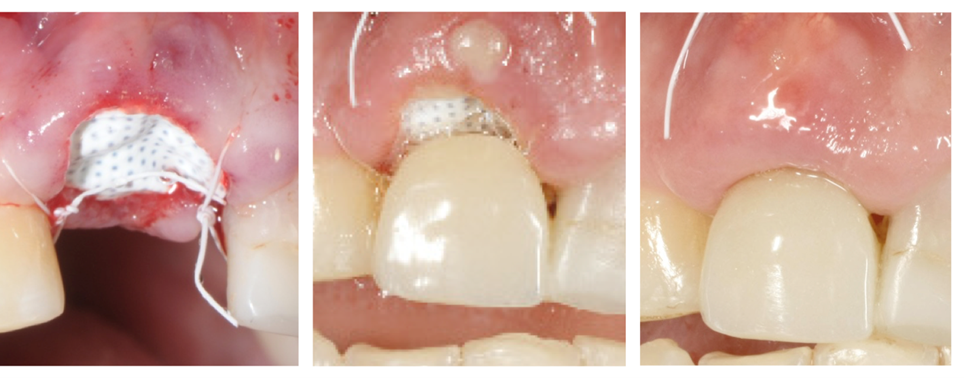

Inserimento della membrana in dPTFE Cytoplast TXT 1224 tramite sutura e posizionamento di sostituto osso suino ad alta porosità Zcore™.

Tre momenti: al momento della chirurgia, dopo 1 settimana e dopo 4 settimane